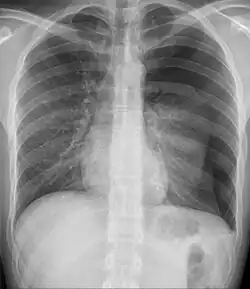

- Pleural effusion[1]

- Pleural effusion[4]